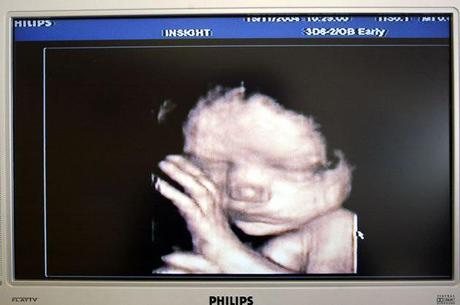

Los investigadores creen que las imágenes de las ecografías 4D difundidas muestran una tendencia que se repite: la ansiedad o preocupación en la madre tiene un efecto directo -al menos temporal- en las reacciones del bebé en el útero, que busca tocarse la cara. Suponen, desde la Universidad de Durham, que se trata de un gesto con el que “calmarse” o darse seguridad. Las imágenes fueron tomadas con un moderno escáner especial 4D que realiza una composición de fotografías normales planas, desde diferentes ángulos, para crear una sensación de tres dimensiones en la imagen, que muestra con bastante fidelidad el interior del útero. Con este método, se realizaron diversas ecografías a 15 madres, cuatro veces durante sus embarazos. A la vez, se les hacía una encuesta sobre las situaciones que vivían y si se sentían estresadas. De las 57 ecografías realizadas en total, estos fetos llegaban a tocarse la cara un total de 342 veces. Los investigadores encontraron una relación directa: cuanto más estrés, presión o ansiedad contaban las embarazadas, más veces se tocaban la carita con la mano izquierda sus hijos. Hablan de la primera evidencia fotográfica de que los fetos sienten nuestro malestar. Otros estudios de los últimos años ya sugieren que el estrés materno que sufren en el vientre puede afectar a su desarrollo neuronal, ya que se disparan los niveles de cortisol en el útero, aunque no se tiene claro hasta dónde puede influir.